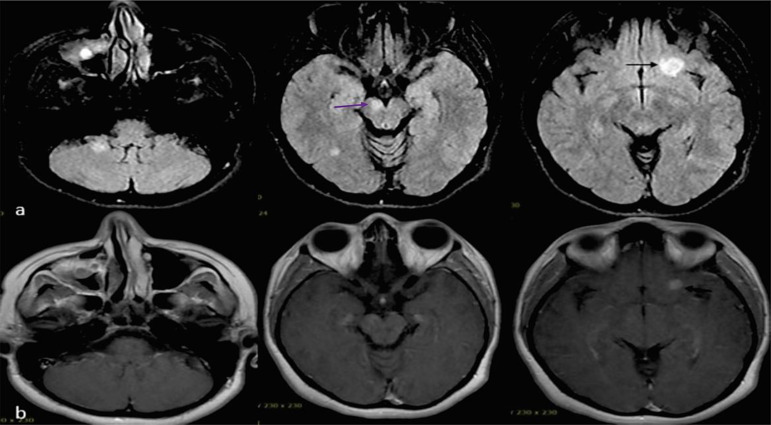

背景:多发性硬化症(MS)是导致年轻人非创伤性残疾的最常见原因。关于接种 2019 年冠状病毒病(COVID-19)疫苗后发生脱髓鞘事件的报道很有限。接种方法我们报告了所有在2021年9月至2022年6月期间新诊断为多发性硬化症且近期(≤6周)接触过国药集团(BBIBP-CorV)疫苗的患者(n = 8)。我们还查阅了截至 2023 年 9 月发表的相关文献。结果在研究期间,338 名新确诊的多发性硬化症患者到我们的多发性硬化症三级转诊中心就诊,其中 8 人(2.36%)在接种国药控股疫苗后首次脱髓鞘发作,中位间隔为 2 [2.0, 4.0] 周(性别比为 1:1,中位年龄:20.5 [18.0, 27.0] 岁)。除一名患者有潜在脱髓鞘病史和另一名患者有免疫性血小板减少性紫癜(ITP)家族史外,其他患者均无自身免疫/神经系统疾病的个人或家族病史。所有患者均有脱髓鞘性脑部磁共振成像病变,其中4人的颈脊髓受累。最常受影响的脑区是脑室周围和皮层下区域。所有患者的寡克隆带(OCB)均呈阳性,支持多发性硬化症的诊断。所有患者均被诊断为复发性多发性硬化症,并接受了单独或结合血浆置换的静脉甲基强的松龙(IVMP)治疗(3/8)。利妥昔单抗是最常用的疾病修饰治疗方法(3/8)。结论本研究提供了初步证据,证明国药控股疫苗与多发性硬化症初期表现之间存在潜在联系。然而,要证实这种关联并确定其潜在机制,还需要进行更大规模的对照组研究和长期随访。

Background: Multiple sclerosis (MS) is the most common cause of non-traumatic disability in young individuals. There are limited reports of developing demyelinating events following the coronavirus disease 2019 (COVID-19) vaccination. Methods: We reported all individuals (n = 8) with new MS diagnoses with recent exposure (≤ 6 weeks) to the Sinopharm (BBIBP-CorV) vaccine between September 2021 and June 2022. We also reviewed the related literature published as of September 2023. Results: Of 338 newly diagnosed patients with MS who attended our tertiary referral MS center during the study period, 8 (2.36%) had their first demyelinating attack with a median interval of 2 [2.0, 4.0] weeks following the Sinopharm vaccine (sex ratio 1:1, median age: 20.5 [18.0, 27.0] years). No personal or family history of autoimmune/neurological disorders was documented, except for one patient's history of a previous potential demyelinating event and another's family history of immune thrombocytopenic purpura (ITP). All patients had demyelinating brain MRI lesions, and 4 had cervical spinal cord involvement. The brain areas most commonly affected were the periventricular and subcortical regions. Positive oligoclonal bands (OCBs) in all patients supported the MS diagnosis. All patients were diagnosed with relapsing-remitting MS and received intravenous methylprednisolone (IVMP) alone or in combination with plasma exchange (3/8). Rituximab was the most frequently used disease-modifying treatment (3/8). Conclusion: This study provides preliminary evidence of a potential association between the Sinopharm vaccine and the initial manifestations of MS. However, further larger-scale studies with control groups and long-term follow-ups are needed to confirm this association and determine the underlying mechanisms.